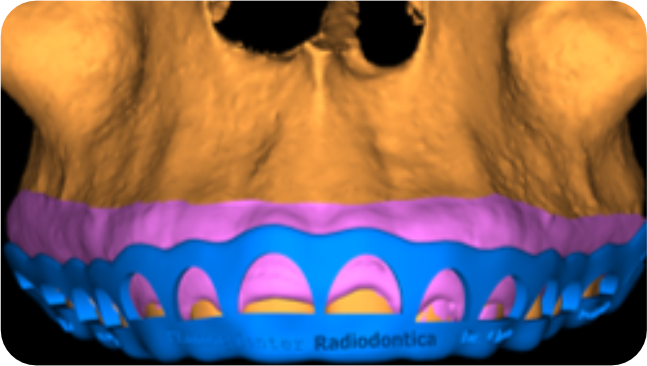

A Periodontia pode ser otimizada com a utilização dos recursos digitais, através do planejamento e o uso de guias para remoções ao redor dos dentes, aumenta a previsibilidade e a segurança da cirurgia. Esta guia é chamada de Perioguide, ou um guia para Periodontia.

Atualmente, diversas técnicas de cirurgia plástica gengival vem sendo utilizadas para aumentar a precisão dos recortes gengivais estéticos, mas engana-se quem pensa que a gengivoplastia é somente a remoção da gengiva em excesso. Cuidados pós-operatórios, tempo de repouso, cicatrização, simulações e muitos outros detalhes estão envolvidos neste procedimento cirúrgico que surpreende pela delicadeza e complexidade.

Com as transformações do sorriso com lentes de contato dental, a gengivoplastia ocupa os primeiros lugares entre os procedimentos estéticos mais realizados nos consultórios odontológicos. Além de alinhar gengivas, esta delicada cirurgia também pode ter funções tão distintas como eliminar o sorriso gengival ou melhorar os resultados estéticos de tratamentos com próteses dentárias, ou facetas de porcelana – ou simplesmente melhorar a harmonia do sorriso.